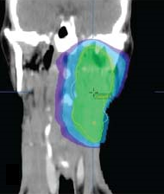

Stage IVA HPV-positive squamous cell carcinoma of the head and neck